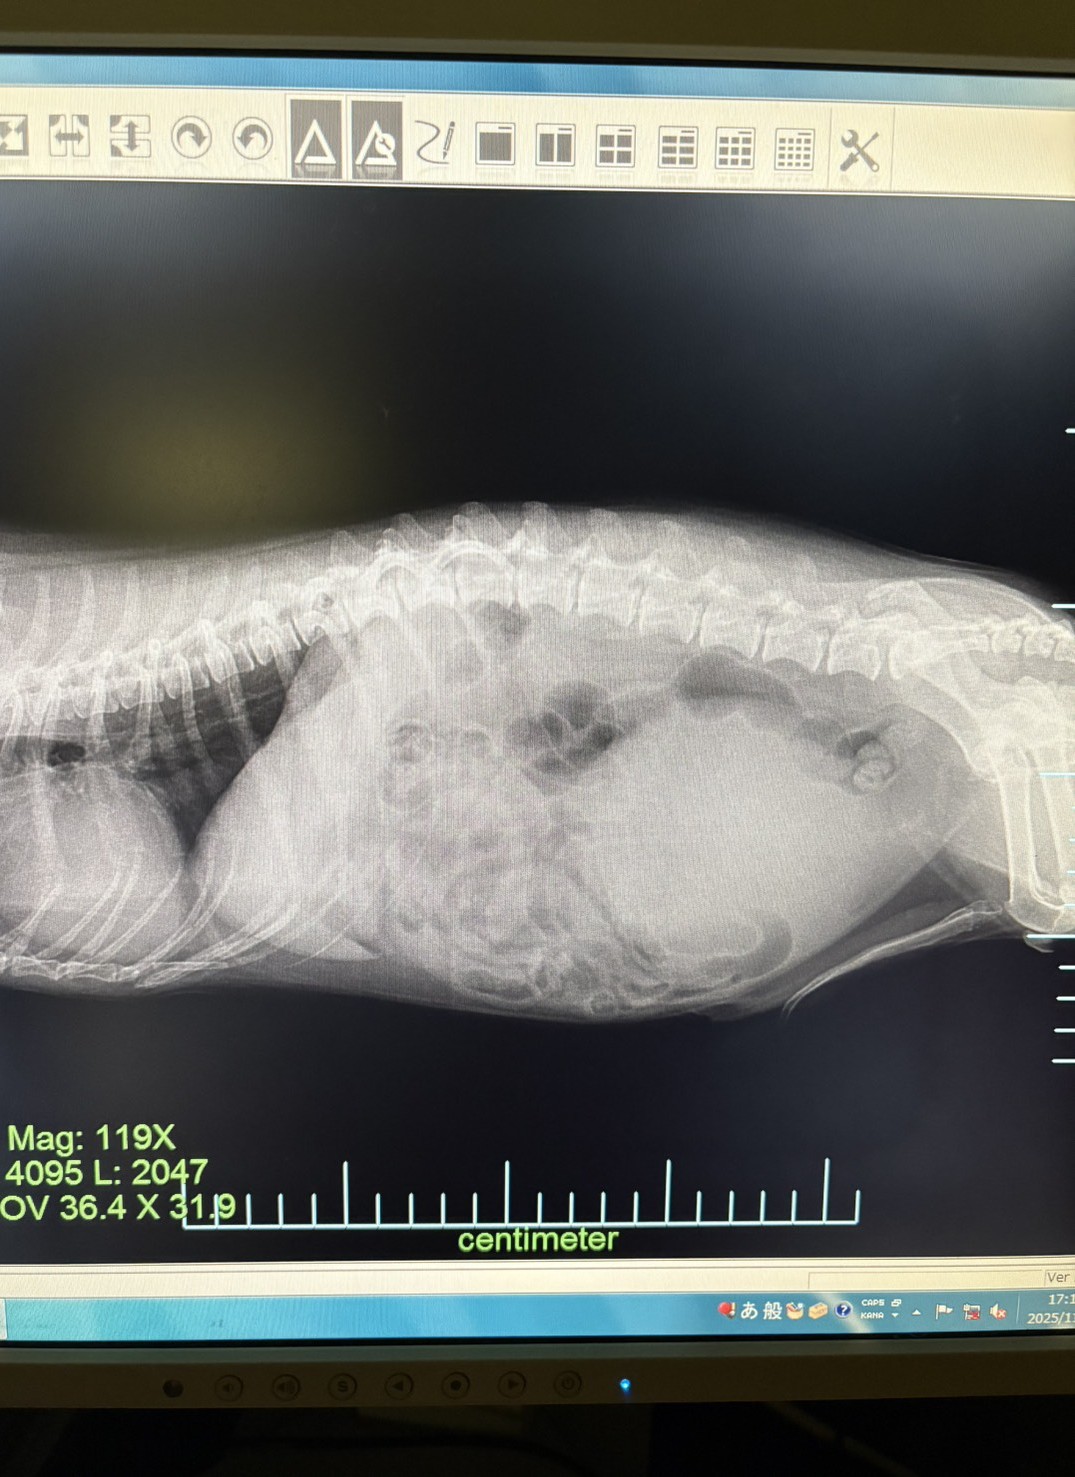

レントゲンに映ったお腹の腫瘍です。

レントゲン、超音波検査、血液検査などを行いお腹の中の腫瘍を確認しました。

お腹の中の大きな腫瘍は、精巣が正常な位置におりずに、お腹の中で精巣が腫瘍化してしまったものでした。

取り出した腫瘍は10センチ弱の大きな腫瘍でした。重みも400gあり、わんちゃんはだいぶ痩せてしまっていましたが、大きな問題なく無事に摘出できました。